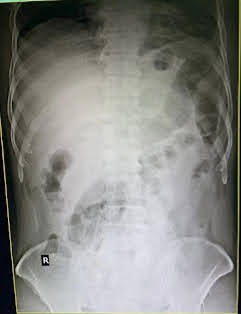

X-Ray

Diagnosis:

Acute Pancreatitis